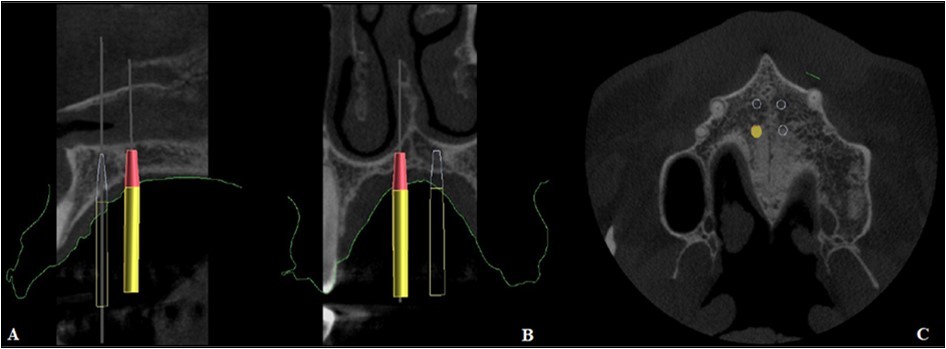

Figure 4.Positioning of the mini-implants on CBCT, A. Sagittal section, B. Coronal section, C. Axial section

Positioning of the mini-implants on CBCT, A. Sagittal section, B. Coronal section, C. Axial section

The precise position and angulation of the mini-implants is replicated by 4 cylindrical metallic guides taking into consideration the following parameters: bone thickness, soft tissue thickness and anatomical surrounding structures. The most appropriate site for the placement of mini-implants is: 3 mm lateral to the suture in the first premolar region. (Figure 3,Figure 4)